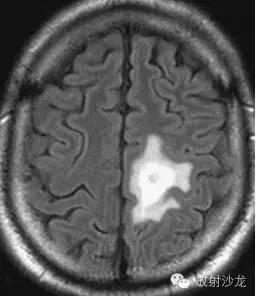

双侧幕上半球放射冠区多发斑片状异常信号区。T1WI(A)为稍低信号,T2WI(B)为高信号,FLAIR(C)呈不均匀稍高信号,占位效应不明显。

肿块样的ms,但较之肿瘤水肿轻,和对白质压迫的作用。